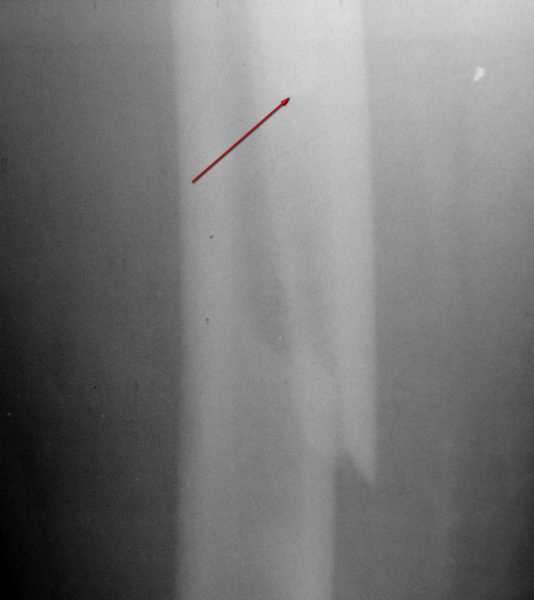

Вот фрагменты этих снимков с более различимыми областями интереса.

Видимо, тут надо добиваться точной репозиции этой спирали вдоль протеза, чтобы воссоздать ложе для ножки.

1. Спасибо за детализацию. Всё увидел.